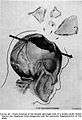

Trajectory of the missile through President Kennedy's skull. The bullet struck posterior part of his right parietal bone from behind.- Cephalic extremity.Original mummification.